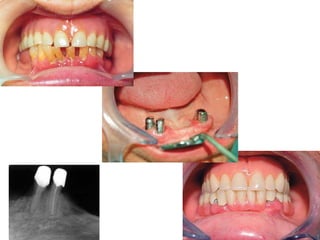

Clinical Procedures

I-Abutment preparation:

-Crown reduction and contouring with or

without endodontic treatment

- Periodontal treatment.

II-Primary impression:

alginate impression in stock tray.

III- Special trays constructed on primary

cast.

Preparing the Abutments

1. Maximum Reduction of the Coronal Portion

2. Crown-root ratio

3. No interference with artificial tooth placement

4. Restoration and polishing

Crown reduction

III- Secondary impression

Made using rubber base stone

Secondary impression is made using rubber

base, pour stone casts

Wax patterns for copings

Casting into metal

Copings are cemented on prepared abutments

Another Impressions are made to obtain casts

for the coping-covered abutments.